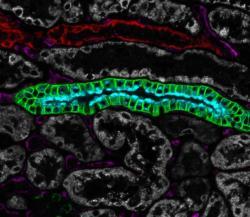

Multiplex tissue image of the month - AQP3 in kidneyThe difference in spatial distributions of two aquaporin proteins in the cells of collecting ducts in the kidney is illuminated through multiplex immunohistochemistry (mIHC/IF). The high contrast visualization of multiple proteins through mIHC/IF makes it possible to distinguish subtle differences in localization between two proteins at the subcellular level. One example is the distribution of aquaporin 2 and 3 in the kidney. These two channel proteins are responsible for water reabsorption in the collecting ducts of the kidney. Aquaporin 2 (AQP2; teal) - utilized as the marker protein for collecting ducts in the mIHC/IF panel for kidney - is localized at the apical part of the cell membrane towards the lumen of the collecting duct to guide the water inside the cell, while AQP3 (green) is distributed along the basolateral part of the cell membrane to shuttle the water further to the interstitial compartment and back into circulation. Other visualized kidney structures include proximal (gray) and distal (red) tubules as well as endothelia (purple). For more details about the mIHC/IF technique visit our method page. |